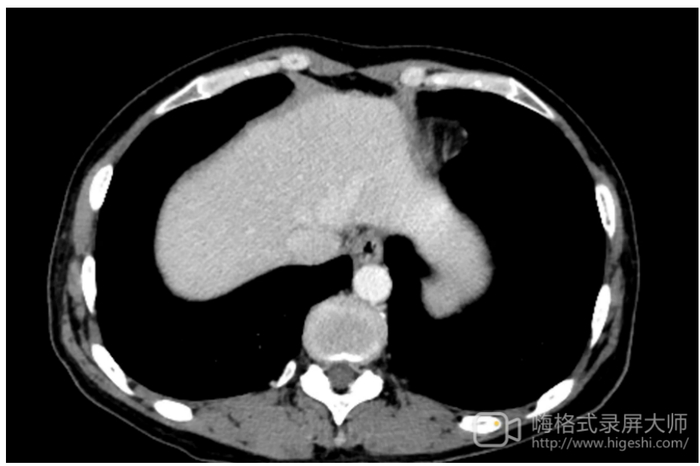

• 2023年2月6日行纤维胃镜检查(图2),提示胃体小弯低回声浸润性病变(T4N3)侵及胃窦和幽门。

用药2周期后,于2023年4月8日复查腹部CT检查(图3),提示胃壁增厚僵硬,以胃体为著,较前好转,考虑胃癌(T4N+);于2023年4月15日复查纤维胃镜检查(图4),提示胃体小弯低回声浸润性病变(T4N3)侵及胃窦,镜下见病灶较前改善,超声表现无明显变化。

用药2周期后,于2023年6月17日复查腹部CT检查(图5),提示胃壁增厚僵硬,以胃体为著,较前略减轻,考虑胃癌(T3N1);于2023年6月24日复查纤维胃镜检查(图6),提示胃体小弯低回声浸润性病变(T3N1)侵及胃窦。